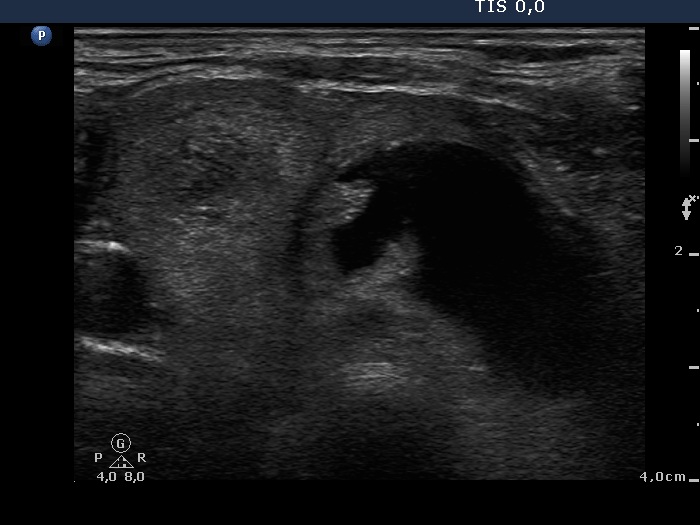

Note the presence of

microcalcifications at the edge of solid part.

After evacuation of the seemingly

simple cyst a small suspicious solid part appeared with

microcalcifications.